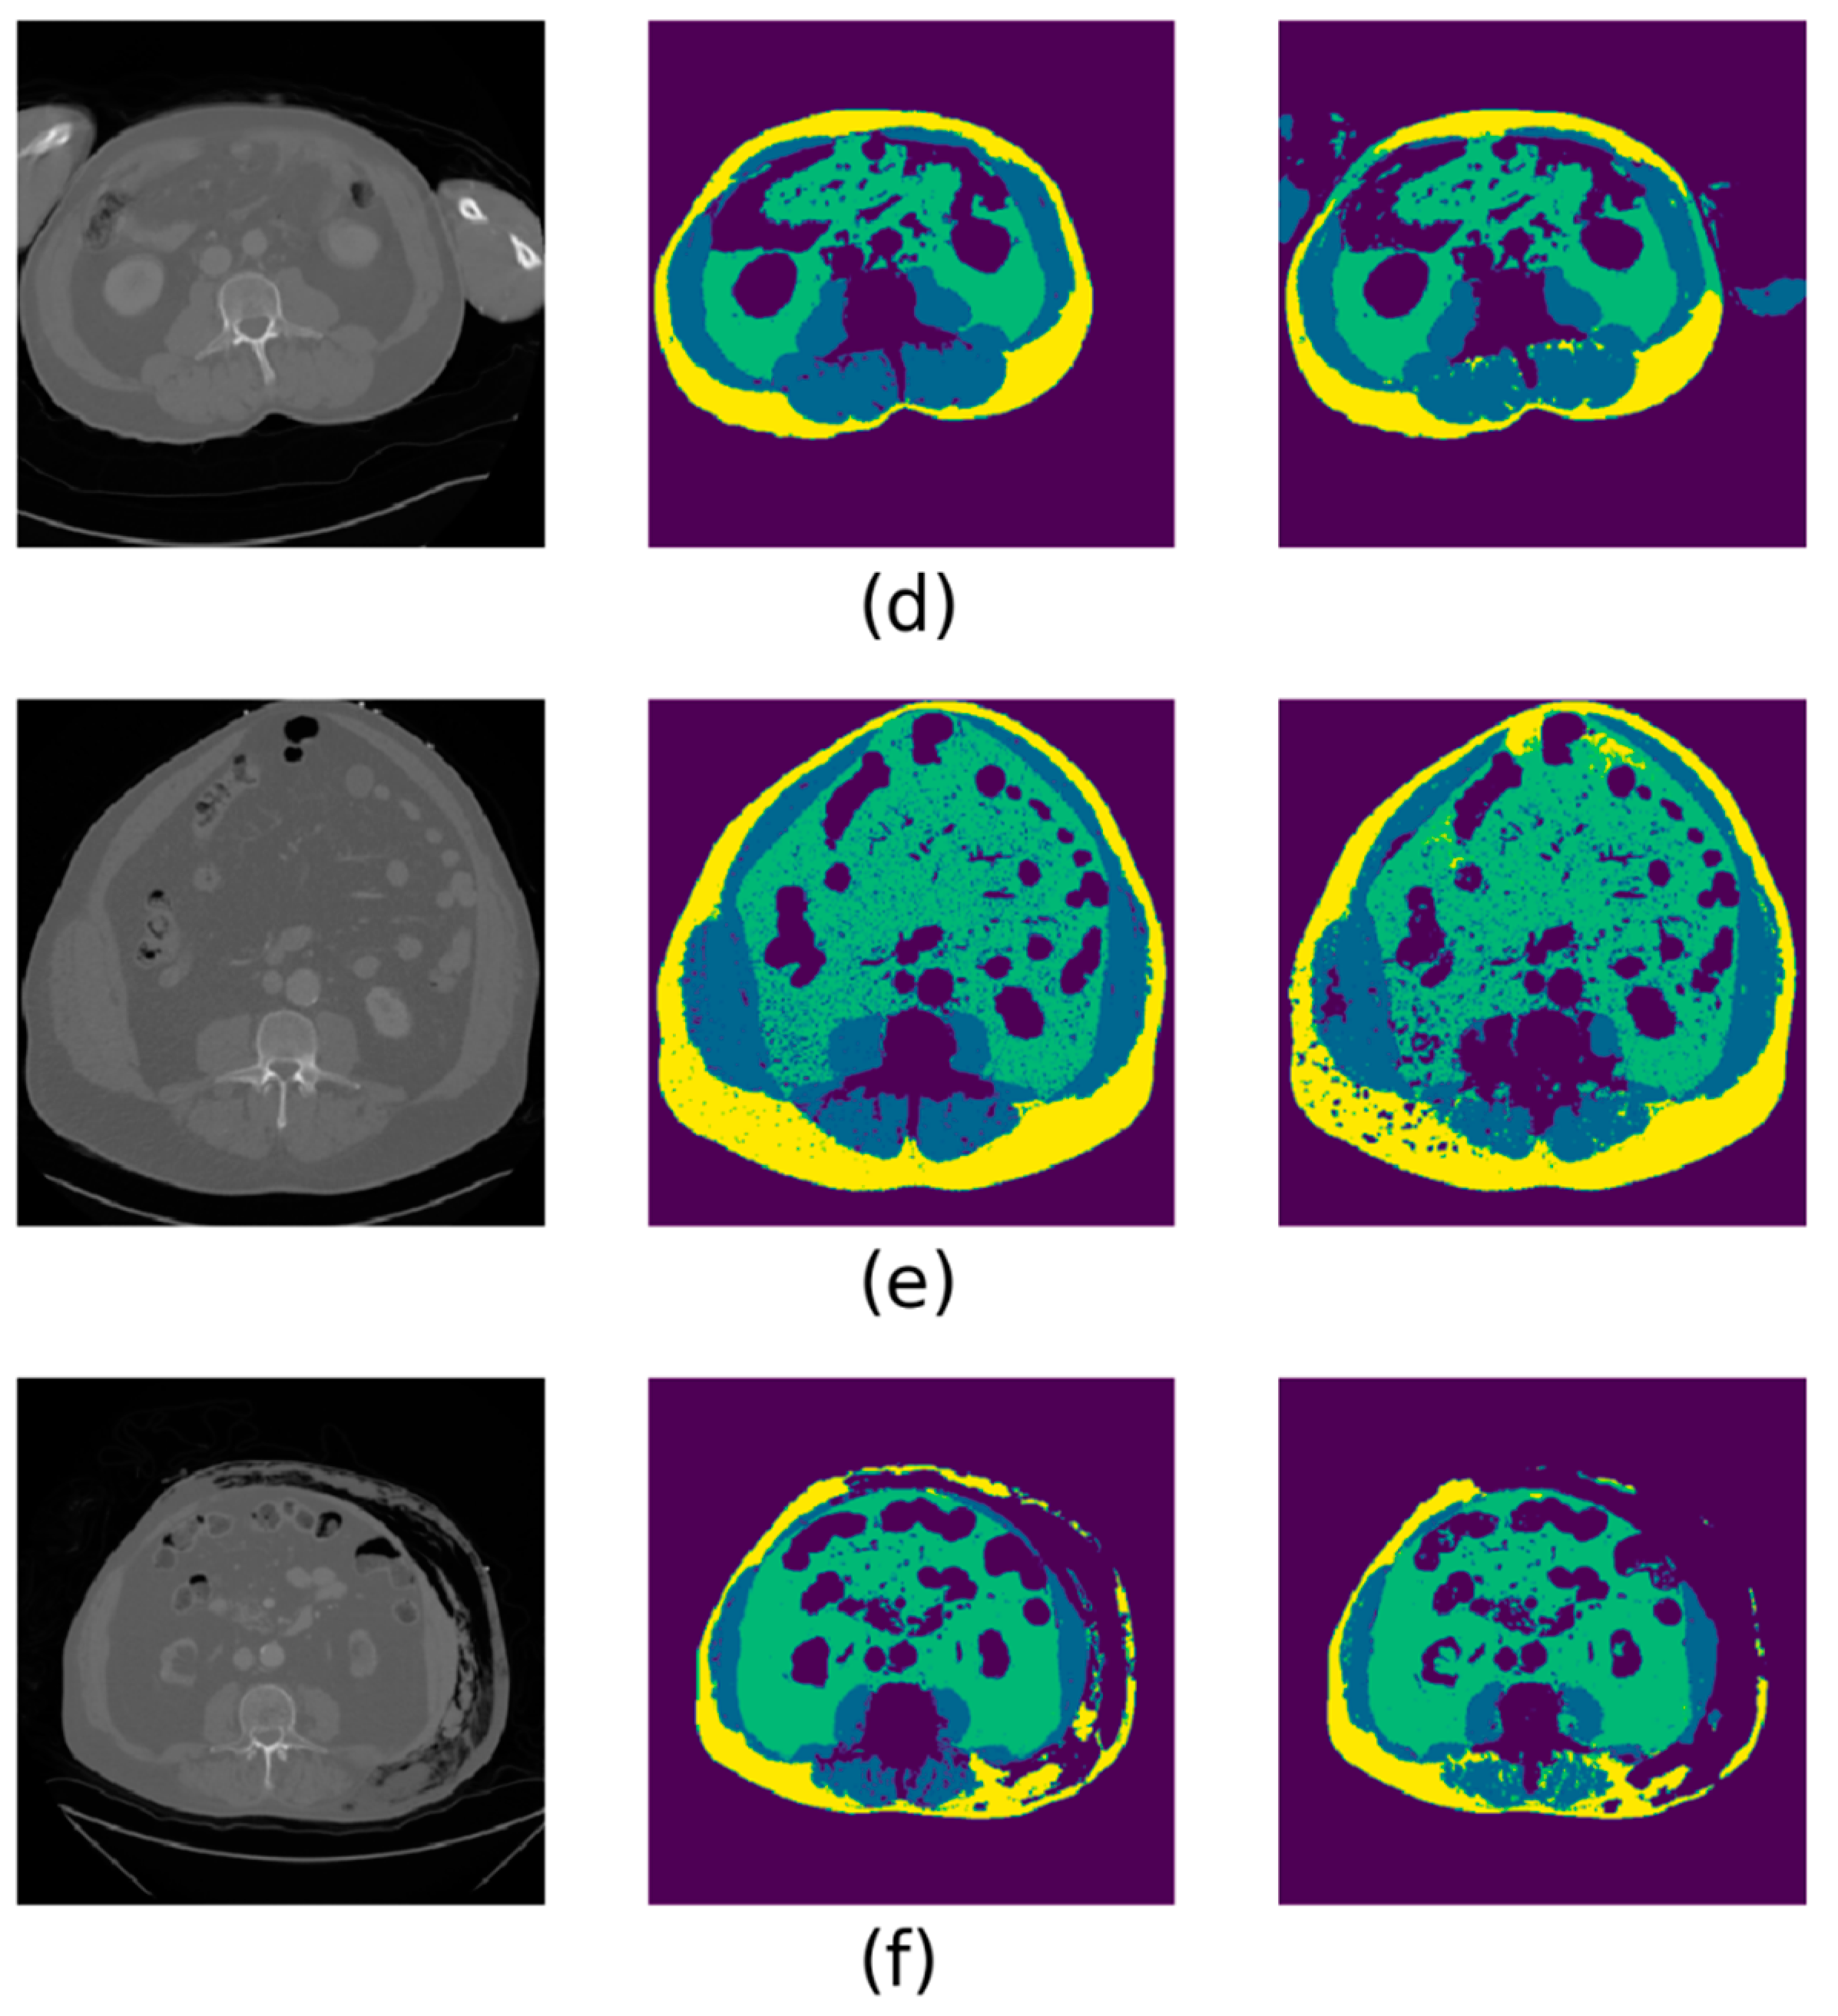

From all 233 individual results of the automated segmentation, we arbitrarily selected six as representative examples of the overall geometric findings. These are presented in Figure 3. The majority of cases with poor automated segmentation performance coincided with unusually noisy or poor-quality CT images. The second most common cause of discrepancies was the appearance of hands and/or arms in the CT field of view, though these were only rarely present in the training dataset. Much rarer trauma cases showing poor automated segmentation results involved the presence of external foreign objects adjacent to the abdomen, atypical anatomy (such as extremely low muscle mass) or clear signs of subcutaneous emphysema.

Figure 3. Selected examples of deep-learning automated segmentation results, with representative errors represented. In each image, the original L3 CT slice is shown on the left, the ground truth segmentation in the middle and the automated segmentation on the right. The color scheme is as follows—yellow: subcutaneous adipose tissue; blue: lumbar muscle; green: visceral adipose tissue. (a) An automatic segmentation that would be deemed clinically acceptable. (b) A CT “streak” scatter artefact near the spine that led to internal organs and adipose being mislabeled. (c) A case of an unknown foreign object lying under the left dorsolateral side of the patient, creating strong scatter artefacts that led to the misclassification of subcutaneous adipose as muscle. (d) A common event in the trauma dataset that was only rarely seen in the training dataset, i.e., hands and arms in the CT field of view being misclassified as lumbar muscle. (e) A noisier CT image than usual, resulting in spots of undetected adipose and muscle. (f) A rare case of post-traumatic subcutaneous emphysema, leading to missed detection of subcutaneous adipose.